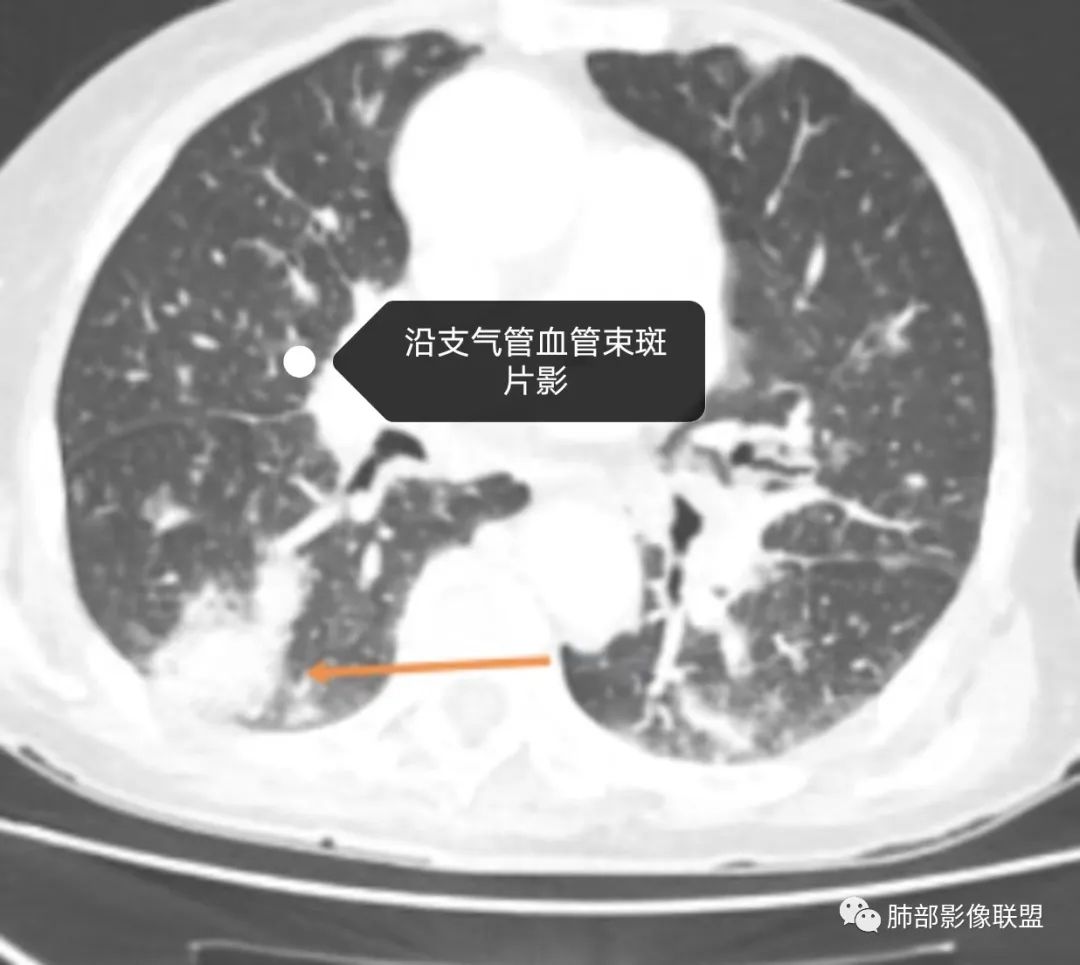

老年女性,发热起病,两肺散在斑片状影,三个月后两肺病灶进展,支气管血管束增厚,结合发热病史、实验室检查LCH增高,肾脏及腹膜后淋巴结肿大,结合以上综合考虑符合淋巴瘤表现。

老年女性,双肺支气管管壁增厚,沿血管束走形分布结节及斑片影,复查病灶增多增大,部分呈点晕征改变,腹部左肾盂软组织密度影,周边淋巴结增大。考虑肿瘤并肺内转移,淋巴瘤?鉴别真菌感染,曲霉菌?

老年女性患者,发热就医,两肺片状影,沿支气管血管束分布,炎性指标升高,糖尿病基础,首诊考虑肺部感染合乎情理,这也是常见病!事实上,患者抗感染治疗好转出院。

三月后患者再次因发热就医,病灶在“原址”基础之上范围扩大,病灶增多(而非此起彼伏),就有些不同寻常,仅如此高龄,如此大范围感染,持续三月之久?太难以想象。

两肺多发病灶,沿支气管血管束分布,缺乏多形性特点,始终未见空洞,没有此起彼伏,没有其他旁证,血管炎的诊断似乎缺乏支撑。